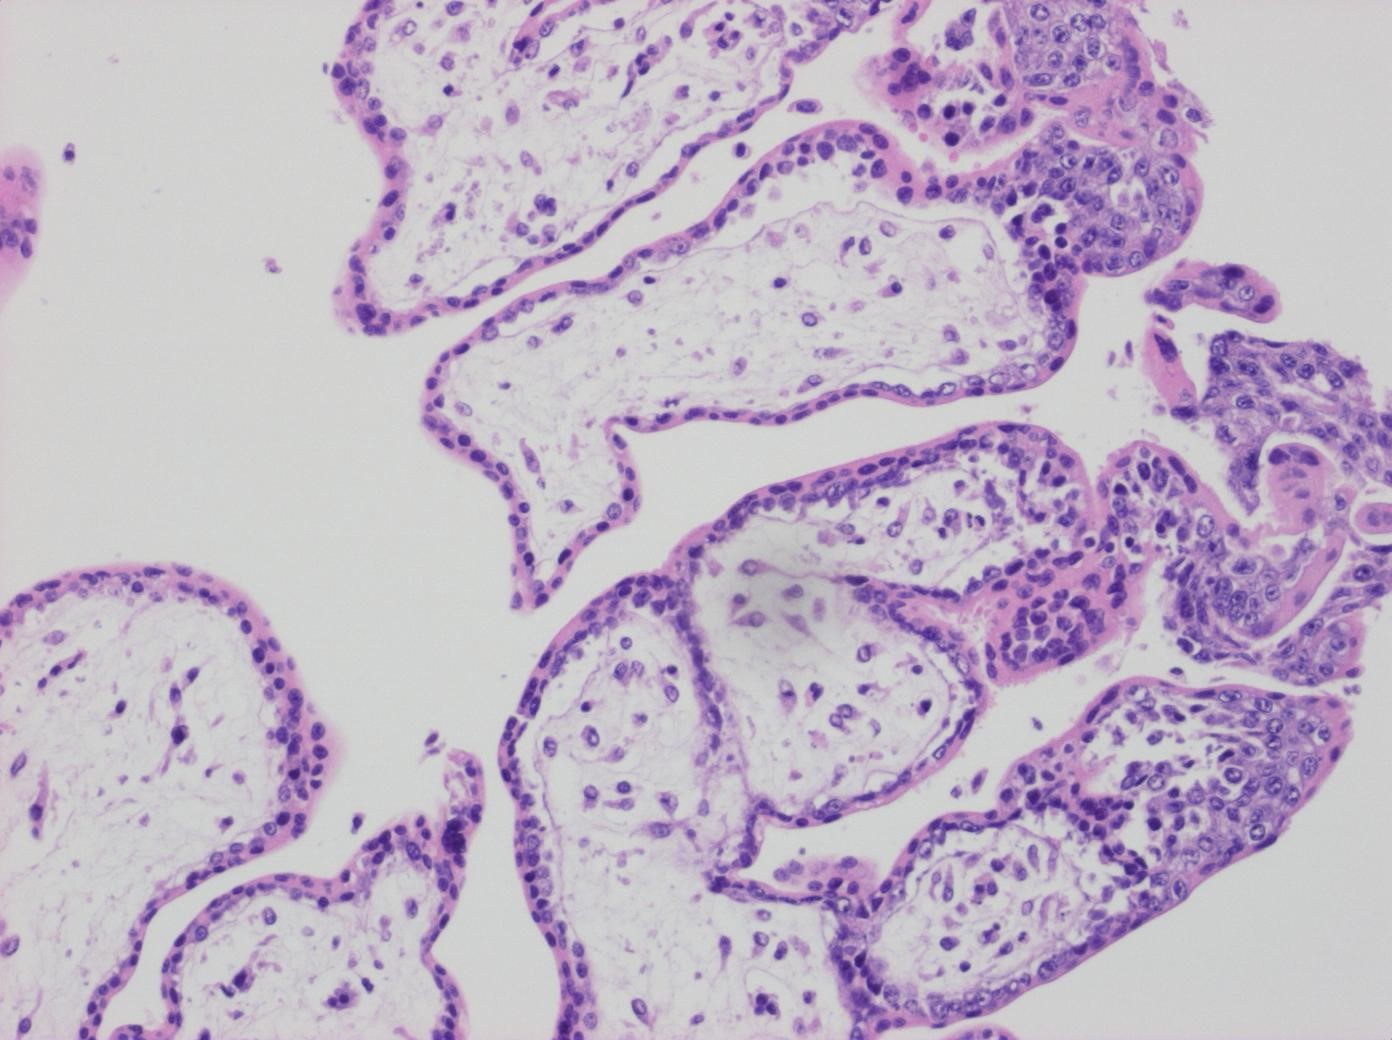

Figur 4. Normala villi HE.

Figur 5. Normala villi p57KIP.